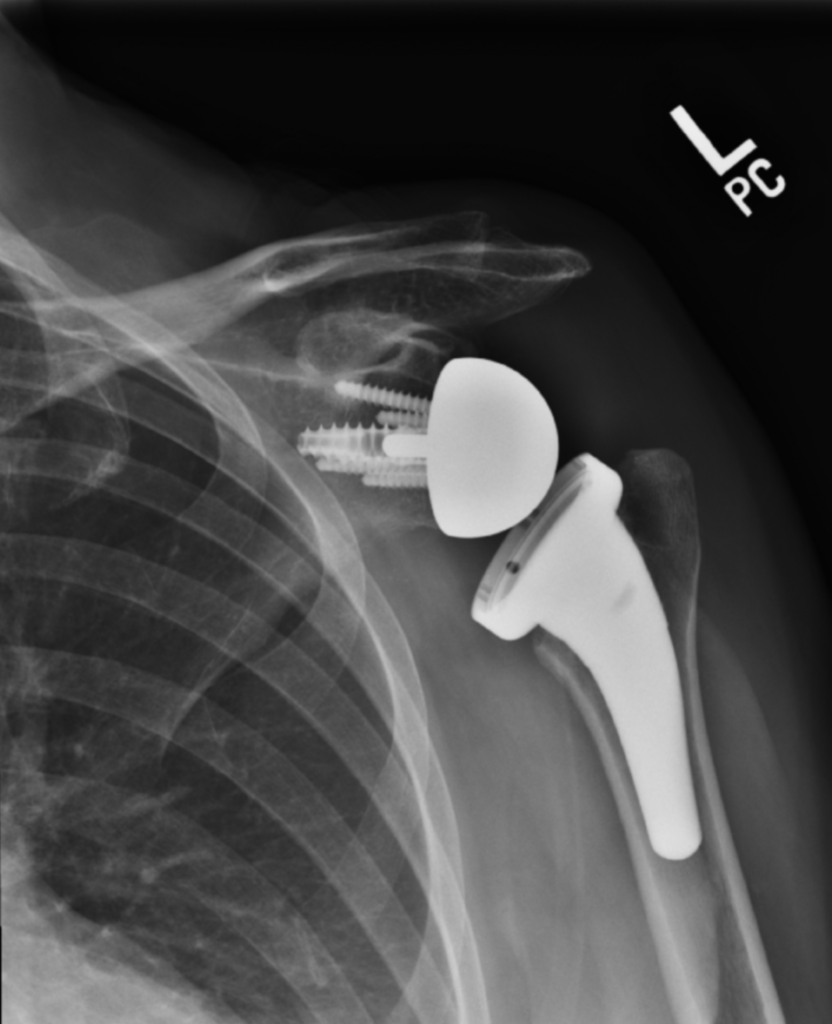

Standard (Anatomic) Total Shoulder Replacement | Dr. Gordon Groh

Partial or Total Shoulder Replacement | Dr Skedros Orthopaedics

Shoulder X Ray post Operation – Radiology Imaging

Reverse Shoulder Replacement FAQ’s – Kyle McClintock, DO | Shoulder and …